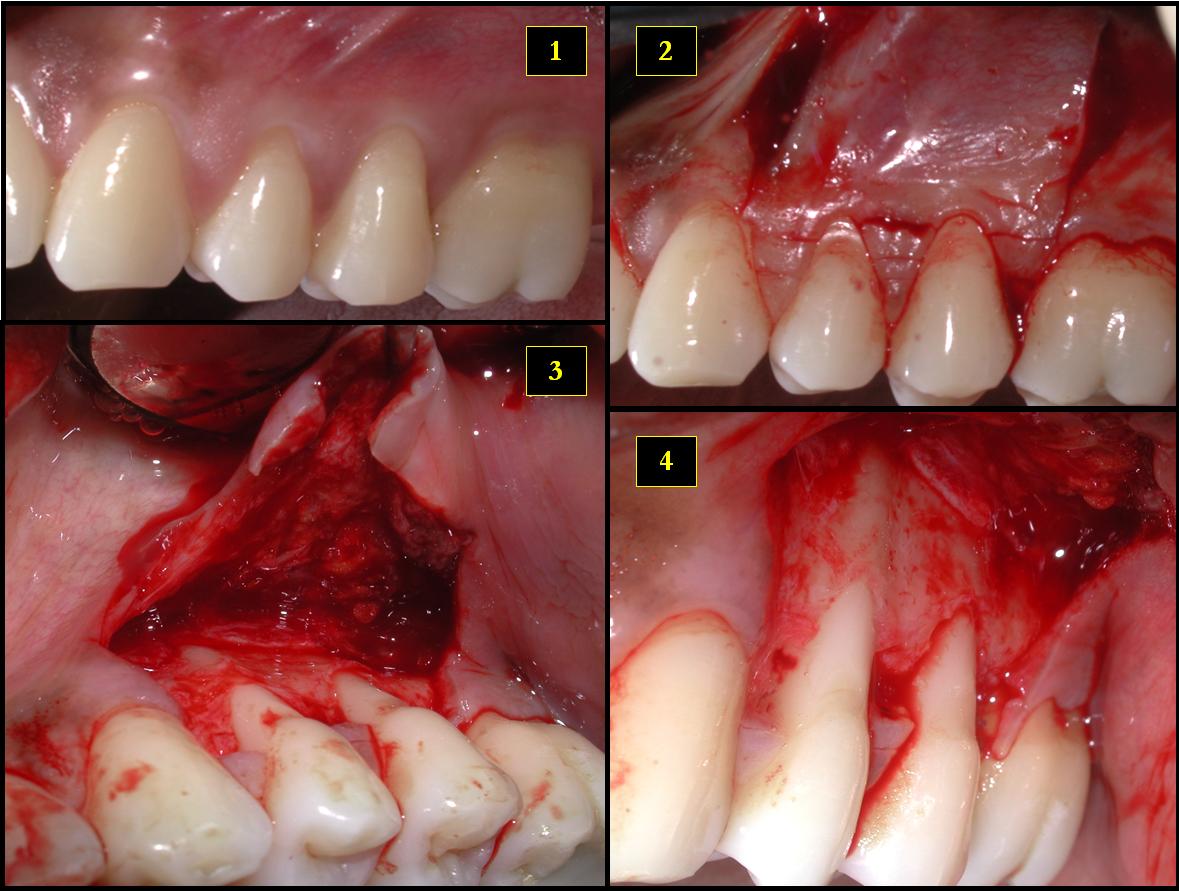

Cirugía de colgajo / Flap surgery

Descripción: Clinical examination revealed 7-mm probing depths, circumferentially around a mandibular implant, bleeding on probing, and the presence of exudate and gingival inflammatory edema

Gingival flap surgery is a type of gum procedure. The gums are separated from the teeth and folded back temporarily. This allows a dentist to reach the root of the tooth and the bone.